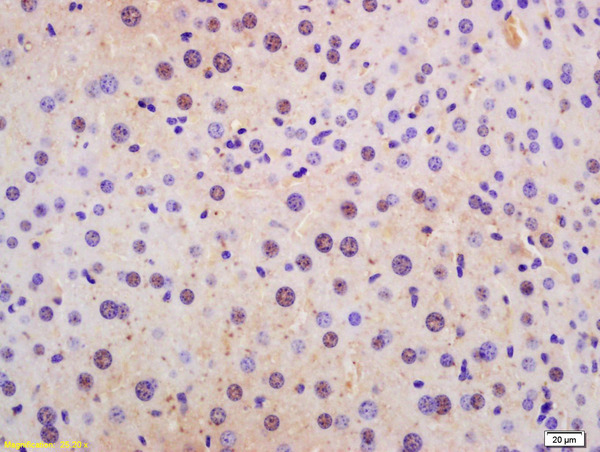

- Main image

- Experimental details

- Formalin-fixed and paraffin embedded rat liver labeled with Rabbit Anti Phospho-p53BP1 (Ser1778) Polyclonal Antibody, Unconjugated (bs-11222R) at 1:200 followed by conjugation to the secondary antibody and DAB staining

- Sample type

- Rat

- Other comments

- Liver